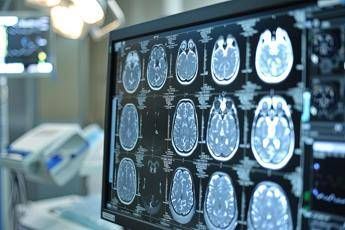

Le apparecchiature, “per ogni spoke e hub, si compongono di una stazione robotizzata con un monitor, telecamera e altoparlante per vedere il paziente in televisita o teleconsulto - spiega Biondina - Negli spoke, a differenza degli hub, ci sono anche i dispositivi per la valutazione dei parametri vitali. Le dotazioni dialogano con le strutture aziendali. Per i pazienti con sospetto ictus ischemico che arrivano in pronto soccorso (Ps) di centri spoke, dove non c’è la neurologia, il medico di Ps può chiedere la televisita o condividere esami di imaging diagnostico con il centro hub. Gli spoke di Asl Salerno - precisa l’ingegnere - permettono ai pazienti di effettuare tac e angiotac con o senza mezzo di contrasto visibili al neurologo a decine di chilometri di distanza”.